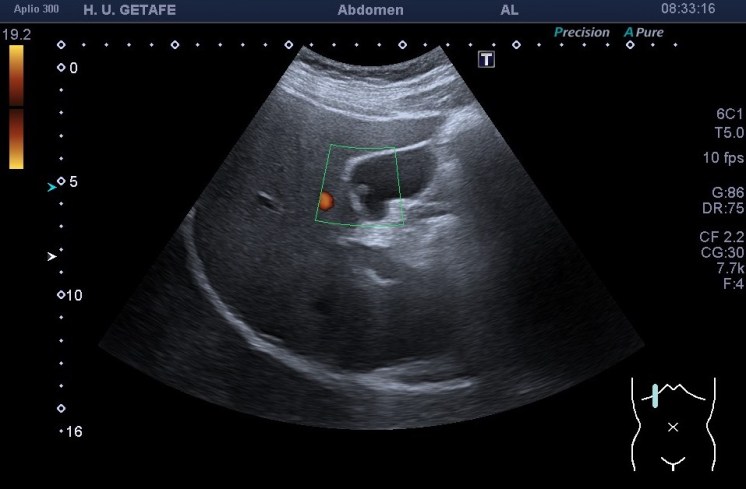

El estudio del pólipo tras su localización se realiza en dos proyecciones, variando al paciente de posición para ver si se mueve. Ponemos doppler, tanto color como modo angio, con el objetivo de demostrar un vaso en el interior del pólipo, que lo delataría como una estructura de aspecto maligno y debería ser valorado por el radiólogo y por el cirujano convenientemente. Por eso ajustar el doppler es muy importante en este caso también.

Medimos para hacer seguimiento de la lesión si se requiriese así. Aplicamos zoom para estudiarlo detalladamente, a mi me encantan las imágenes en este Canon. El Zoom es muy bueno y el estudio del pólipo gana muchísimo. Hablando del Zoom…

Como muy bien puedes observar el caso es bastante anodino, las imágenes te las he puesto y son la excusa para explicarte el uso del Zoom. Habitualmente es un ajuste ecográfico que no usamos en exceso, solo puntualmente, puede pixelar en exceso la imagen, como cuando hacemos una foto con nuestro móvil y la ampliamos con el gesto de nuestros dedos…pixelamos la imagen, perdemos resolución, pero lo nuevos equipos, ganan en esto también y con las sondas de baja frecuencia podemos conseguir imágenes muy bonitas de alguna ecoestructura pequeña y que nos interese medir bien, y este caso me resultó muy plástico y te lo quería explicar. Repasamos el concepto de pólipo vesicular y lo enlazamos con el uso del zoom.